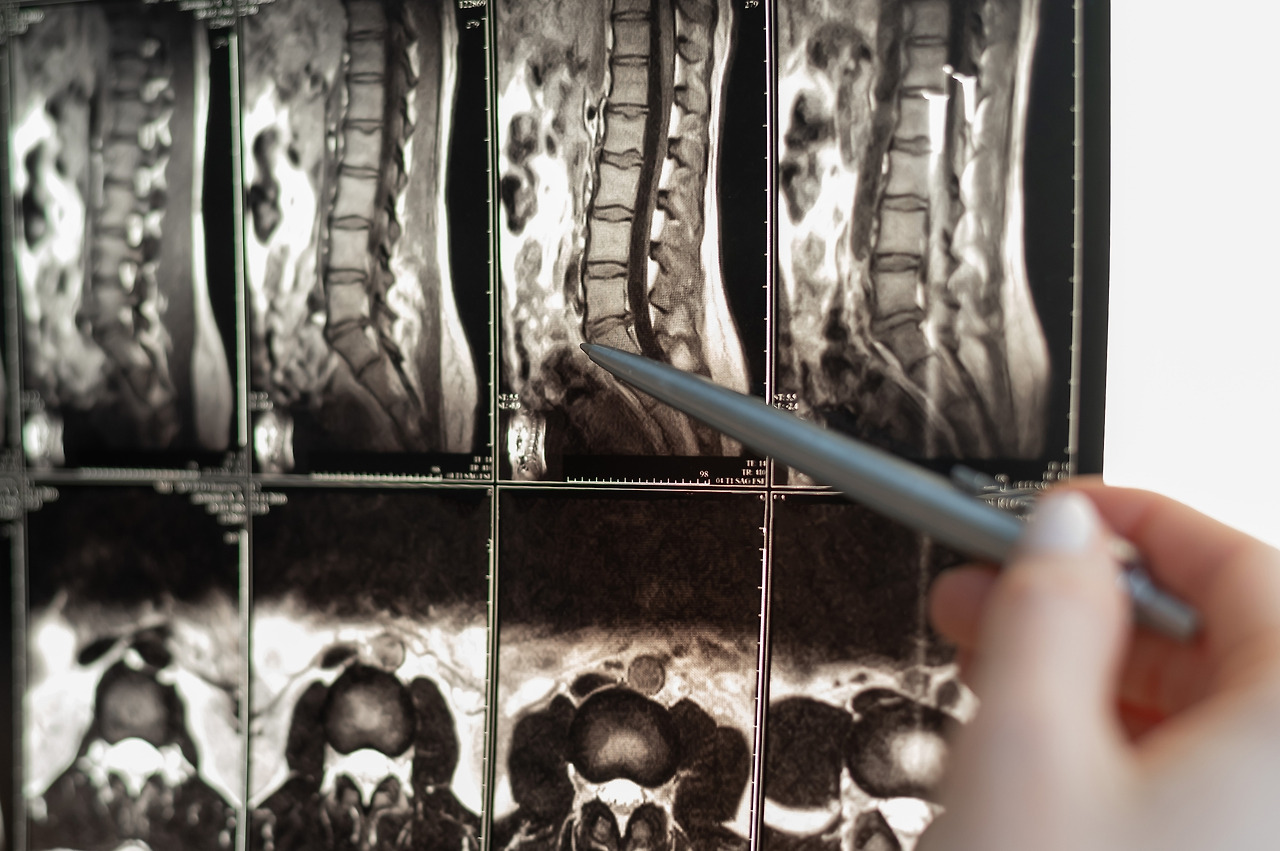

우선 X-Ray, CT, MRI 등 영상학적 검사를 통해 허리 신경성형술이 필요한지를 진단합니다. 아무리 좋은 치료라도 적합한 환자에게 진행해야 효과가 있기 때문에 신경외과 전문의의 진단은 필수입니다. 특히 우리 몸의 기둥으로써 몸을 세우고 지탱함과 동시에 손발을 움직일 수 있게 하는 매우 중요한 신체 부위인 척추에 대한 치료는 신중하고 정확해야 합니다. 척추질환은 골격의 이상뿐 아니라 신경의 이상을 초래하므로 정확한 진단과 그에 맞는 치료가 중요하지요.

pixta_75982696_M.jpg

따라서 에이스병원 척추센터에서는 통증의 조기 해결과 일상생활로의 빠른 복귀를 위해 전문의들이 디스크를 포함한 척추 질환, 두부 및 척추 외상, 말초 신경질환 등 병변에 대해 비수술적 치료와 수술적 치료 중 환자 개인에게 가장 적합하고 안전한 방법을 선택하기 위해 최선을 다합니다. 첨단장비를 이용한 정밀검사와 환자가 느끼는 통증 정도, 그리고 이전 치료 과정 등을 종합해 신경성형술 여부를 결정합니다.